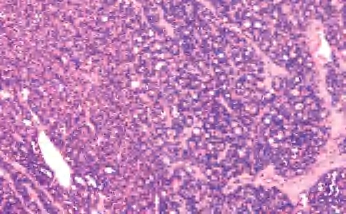

3.镜下 为复杂分支状乳头,含纤维血管轴心,细胞拥挤,核增大,呈卵圆形、沙砾体,表面被以单层柱状上皮,半数以上核呈毛玻璃样,有核沟,核内假包涵体(图3-40至图3-43)。

图3-40 甲状腺乳头状癌

图3-41 甲状腺乳头状癌